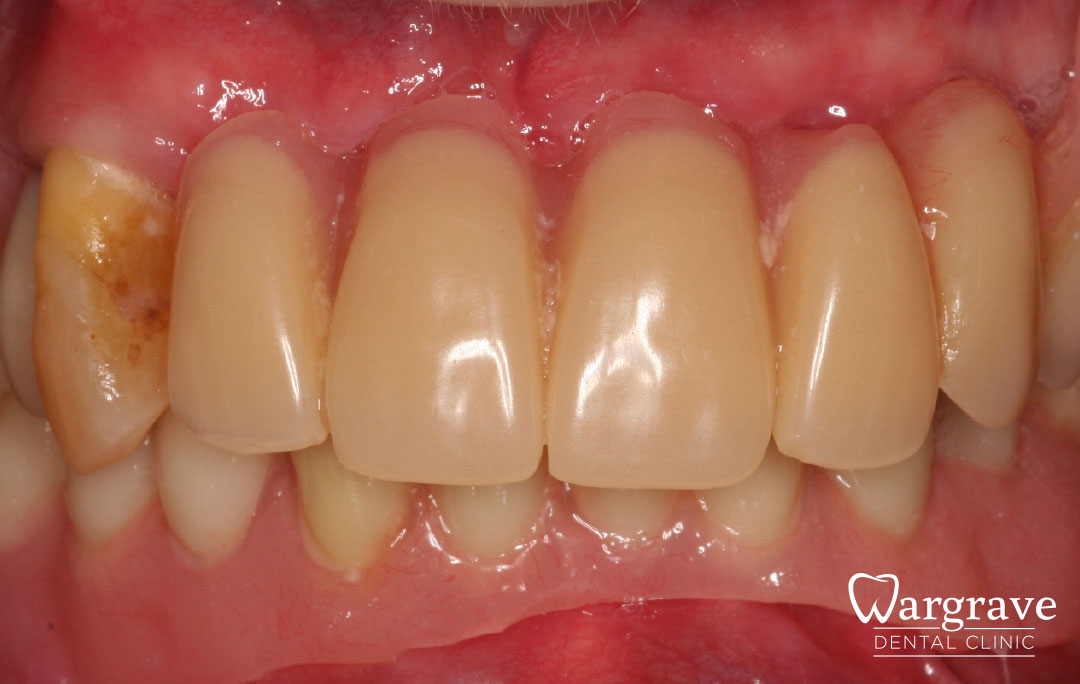

Healthy Smiles These are more advanced examples of different treatments available.All cases shown were carried out by Dr R Khurana unless otherwise stated. Immediate implants Anterior Mandible Bone Regeneration Anterior Mandibular Implant Bridge Maxillary Anterior Implant Bridge Implant stabilised ‘Life Like’ replacement dentures Implant Bridge after 10-years with zero bone loss Implant examples including ZBLC concepts Adhesive Bridge solution for a missing premolar Multidisciplinary care Orthodontics, Replacement veneers and composite bonding Adhesive Bridge solution for missing central incisors Replacement crown, Veneer and Composite Bonding Replacement Crowns and Veneer Injection Moulding using Composite Resin Equilibration Tooth Whitening to treat Developmental Discolouration